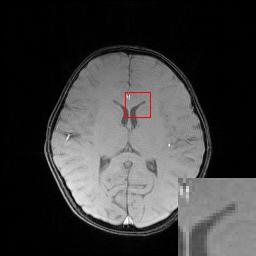

In the CS-MRI inversions, the zero-filled MR images usually serve as the starting point in the iterative optimization. Although the iterative de-aliasing can effectively remove the artifacts and achieve much more pleasing visual quality compared with zero-filled reconstruction, the distortion and information loss is inevitable in the reconstruction. To further illustrate this phenomenon, we compare the pixel-wise reconstruction errors among the zero-filling reconstruction and other reconstruction models of the MR image in Figure 2.

We take the difference between the absolute reconstruction error of zero-filled and the compared CS-MRI methods and only keep the nonnegative values, which can be formulated as

md=(|xfsx¯p||xfs𝒵(y)|)+.subscript𝑚𝑑subscriptsubscript𝑥𝑓𝑠subscript¯𝑥𝑝subscript𝑥𝑓𝑠𝒵𝑦m_{d}={\left({\left|{{x_{fs}}-{\overline{x}_{p}}}\right|-\left|{{x_{fs}}-{\cal Z}(y)}\right|}\right)_{+}}. (8)

Where the operator ()+subscript{\left(\cdot\right)_{+}} set the negative values to zero. We only keep the nonnegative values in the map, which results the filtered difference map. We show the corresponding filtered difference map mdsubscript𝑚𝑑m_{d} in figure 3 in the range [0 0.2]. The bright region means the better accuracy of zero-filled reconstruction. We observe the zero-filling reconstruction provide better reconstruction accuracy on some regions, indicating the information loss in the reconstruction occurs.

Figure 3: The filtered difference map d𝑑d between the reconstruction errors of the zero-filled reconstruction and recent CS-MRI inversions.